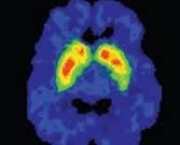

É extremamente assustador a lesão cerebral. Para algo tão maravilhoso e misterioso, na verdade, o cérebro pode ser muito frágil e também suscetível a lesões múltiplas. Os danos no cérebro pode ser causado por um acidente ou por uma infecção, e essencialmente significa a morte das células do cérebro. A mera ideia de dano cerebral, para muitas pessoas, conjura imagens de pessoas em estados vegetativos persistente, ou no mínimo de invalidez mental ou física permanente.

O tempo exato de duração de um dano cerebral, irá depender do tamanho da lesão e onde ocorrer ela. Porém, existem diferentes tipos de dano cerebral e cada um afeta a pessoa de um jeito diferente, sendo mias grave ou não. Um dano leve causado no cérebro, como por exemplo uma concussão, ocorre quando o cérebro salta dentro do crânio, causando laceração e sangramento. O cérebro pode se recuperar incrivelmente vem de machucados pequenos.

Por outro lado, uma lesão cerebral grave, quer dizer que o cérebro sofreu danos extensos. Caso que muitas vezes exige uma cirurgia para aliviar a pressão intracraniana ou remover coágulos. Na maioria das pessoas que sofre um dano grave no cérebro, o resultado é dano irreversível e permanente.

É importante lembrar, que apesar de muitos estudos e técnicas, há ainda muitas coisas desconhecidas sobre o cérebro. Quando uma pessoa sofre uma lesão no cérebro, nem sempre os médicos irão saber se a pessoa será capaz de se recuperar. Há muitos casos também onde pacientes acabam surpreendendo e excedem as expectativas dos médicos. Sendo assim, nem todo dano cerebral é permanente.